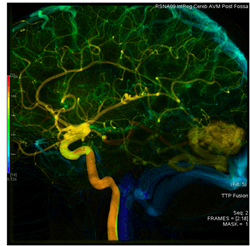

AngioViz uses peak time and density with color as time, and peak density as brightness to show contrast flow timing and magnitud

In one image, AngioViz can show peak pixel density value over an image series. This can indicate relative contrast density and d

AngioViz can show the time that each pixel reaches peak density on a color coded time scale. This helps indicate contrast flow t

AngioViz provides a new visualization of the vascular flow seen in DSA imaging, utilizing a technique called parametric imaging. AngioViz looks at each pixel in the image series and determines two things — the peak value of opacification caused by the contrast, and the time it takes for that pixel to reach peak opacification. These two parameters can be displayed as separate images or combined into a single color-coded image that represents parameters of vascular flow. This enables doctors to perceive parameters of flow quickly to support decision-making. In addition, AngioViz allows easy comparison of parametric images from different DSA acquisitions, such as pre- and post-treatment images. This can help physicians understand the impact on flow dynamics of various interventional treatments.